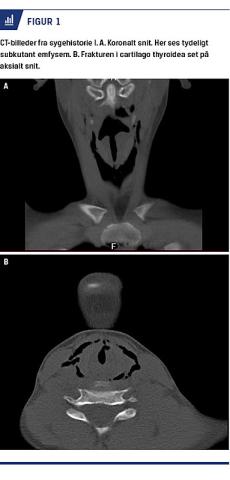

I. En 11-årig pige faldt på en trampolin og slog halsen mod trampolinkanten. Der opstod hæshed initialt. Pigen blev bragt til en akutmodtagelse med ambulance og blev tilset akut af en vagthavende øre-næse-hals-læge. Stemmen blev beskrevet som naturlig, og der var ingen stridor. På halsen fandt man et overfladisk, rødt mærke, og der var palpationsømhed. Ved fleksibel fiberlaryngoskopi fandt man ødem af venstre plica ventricularis, men fri og ikke truet luftvej. En CT viste subkutant emfysem og mulig fraktur i larynx (Figur 1). Pigen blev overflyttet til Rigshospitalet, hvor man fandt en fraktur i cartilago thyroidea, som blev behandlet med kondrosyntese ved åben operation. Hun blev udskrevet dagen efter uden sequelae, men blev fulgt med halvårlige kontroller.

CT anbefales udført i stabil fase. Den kan vise frakturer og emfysem, som ikke kan ses ved fiberlaryngobronkoskopi, som det sås i sygehistorie I. Modsat kan frakturer også udelukkes, og mindre slimhindeskader kan behandles konservativt [4, 5].